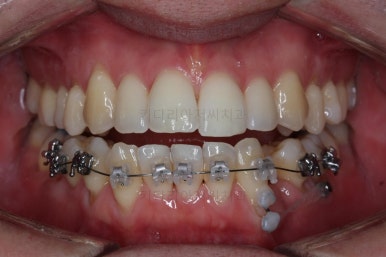

부산비수술교정 키다리아저씨치과에서 시행한 이번 치료의 결과입니다.

옆모습이 주걱턱 느낌이 많이 없어졌고 볼록하던 아랫입술도 뒤로 들어갔어요. 앞니가 거꾸로 물리지 않게 되어 웃거나 말하는 모습도 자연스러워졌어요.

아랫니 갯수가 모자라고 중앙이 맞지 않았고 짝이 안맞는 상황이었으나 비교적 잘 마무리를 했어요.

거꾸로 물리는 상황이 개선되었기 때문에 앞니나 어금니의 교합은 이전과 비교할 수 없을만큼 좋아졌지요.

전후 모습을 비교해 보겠습니다.

왼쪽이 치료 전, 오른쪽이 치료 후 모습입니다.